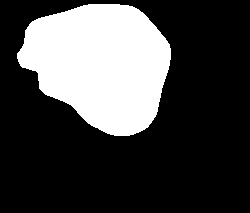

A few sample images and the corresponding masks of the polyp dataset in HyperKvasir are shown in Fig 2. The polyp images are RGB images. The masks of the polyp images are single-channel images with white () for true pixels, which represent polyp regions, and black () for false pixels, which represent clean colon or background regions. In this dataset, there are different sizes of polyps. The distribution of polyp sizes as a percentage of the full image size is presented in the histogram plot in Fig 3, and we can observe that there are more relatively small polyps compared to larger polyps. Additionally, a subset of this dataset was used to prove that the performance of segmentation models trained with small datasets can be improved using our SinGAN-Seg pipeline, and the whole dataset was used to show the effect of using SinGAN-Seg generated synthetic images instead of a large dataset which has enough data to train segmentation models. In this regard, this dataset was used for two purposes:

After training SinGAN-Seg models, we generated random samples per real image using the input scale , which is the lowest scale that uses a random noise input instead of a re-scaled input image. For more details about these scaling numbers and corresponding output behaviors, please refer to the vanilla SinGAN paper [56]. Three randomly selected training images and the corresponding first synthetic images generated using scale are depicted in Fig 4. The first column of the figure represents the real images and the ground truth mask annotated from experts. The rest of the columns represent randomly generated synthetic images and the corresponding generated mask.

In total, we have generated synthetic polyp images and the corresponding masks. SinGAN-Seg generates random samples with high variations when the input scale is . This variation can be easily recognized using the standard deviation (SD) and the mean mask images presented in Fig 5. The mean and SD images were calculated by stacking the generated mask images corresponding to the synthetic images related to a real image and calculating pixel-wise std and mean. Bright color in std images and dark color in mean images mean low variance of pixels. In contrast, dark color in std and bright color in mean images reflect high variance in pixel values. By investigating Fig 5, we see that small polyp masks have high variance compared to the large polyp mask as presented in the figure.